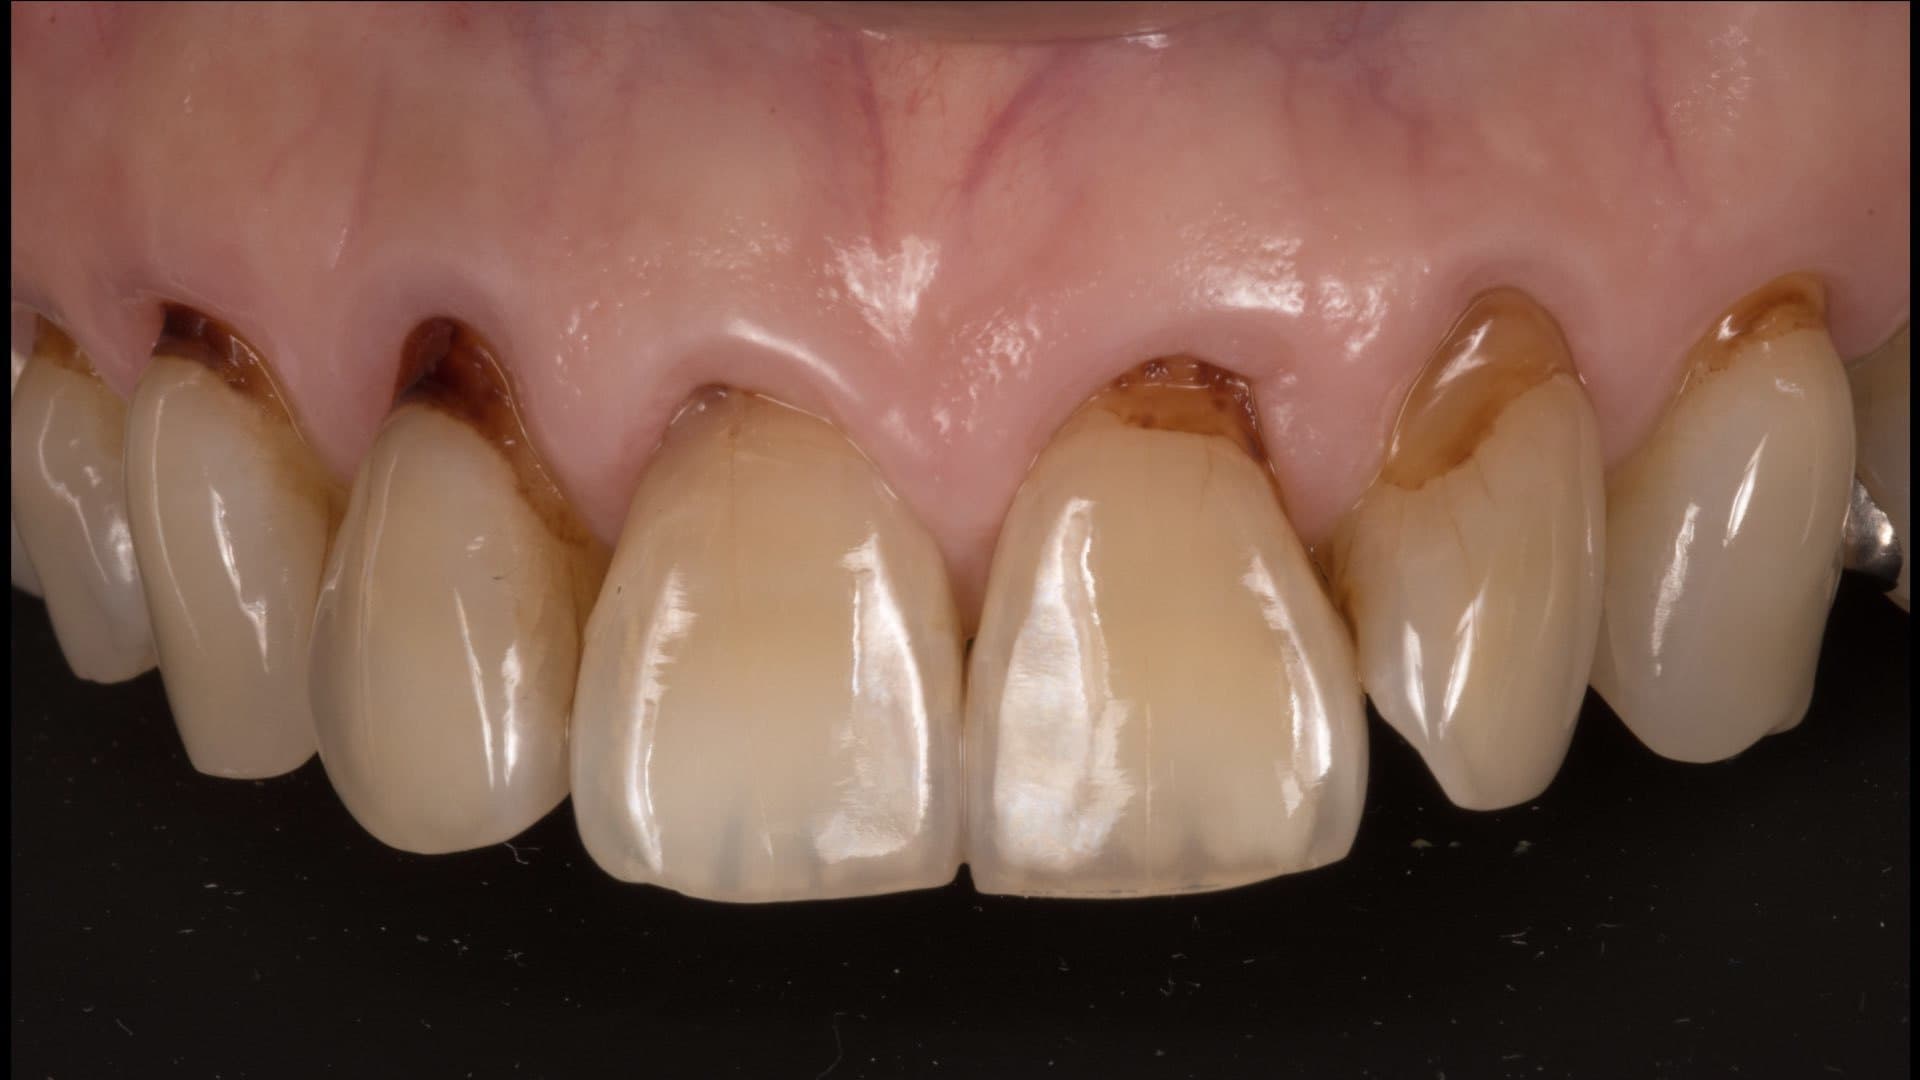

正確な診断を行います

全ての治療は診断からスタートします

あらゆる検査からの情報を分析します

基本的な検査だけでなく、CT検査、歯周病に特異的な細菌のPCR検査、噛み合わせの検査、生活習慣の見直しなどを行います